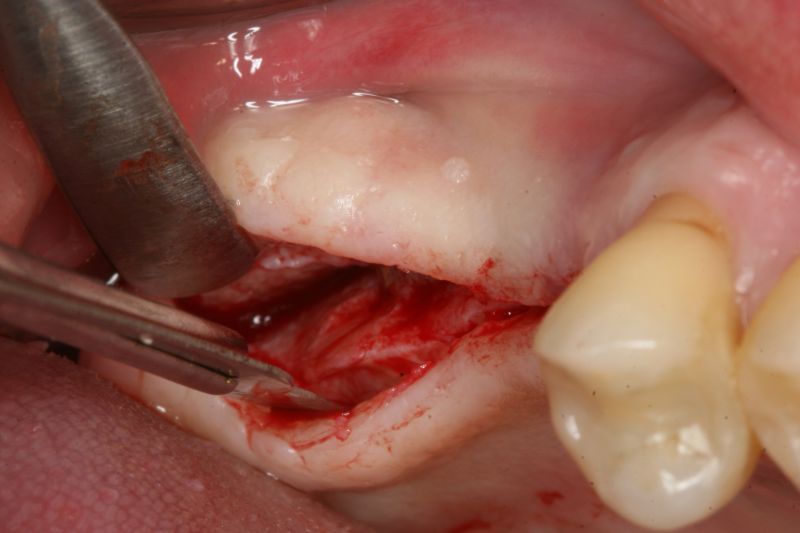

Pre-surgical probing reveals a deep intrabony defect on the distal aspect of the upper canine.